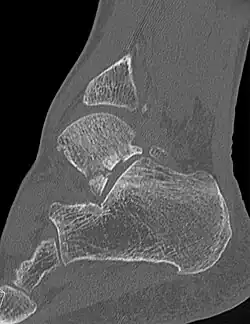

Die Verletzung stellt sich mit Schmerzen und Schwellung in der Fußwurzel und außen am Fuß dar. Diese Befunde können leicht mit einer Verstauchung, Zerrung oder einem Bänderriss am Außenknöchel verwechselt werden. Dieses insbesondere, wenn nicht bekannt ist, dass es sich um einen Snowboarder handelt. Auch ist der Knochenbruch auf Übersichtsröntgenbildern manchmal schwer zu erkennen. Eine Computertomographie kann die Bruchlinien überlagerungsfrei darstellen und ist für die Planung der richtigen Therapie hilfreich.[6][14][7][12]